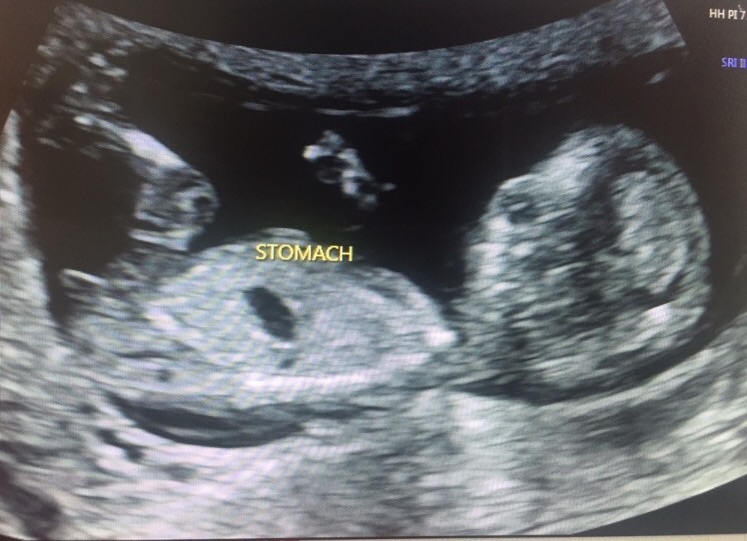

Hi I'm new. What do you think this little babe of mine is? These are my only nub but I have a ramzi photo and skull.

Under 12 weeks they all look girly, but at around 12 weeks the boy nub starts to rise. At 12+2 I'm going to say that this looks very girly.

Girl [emoji175]! That's how my DD's nub looked at my scan that was 12w5d, but she was measuring 13w3d. She too had her legs pulled up to her chest.